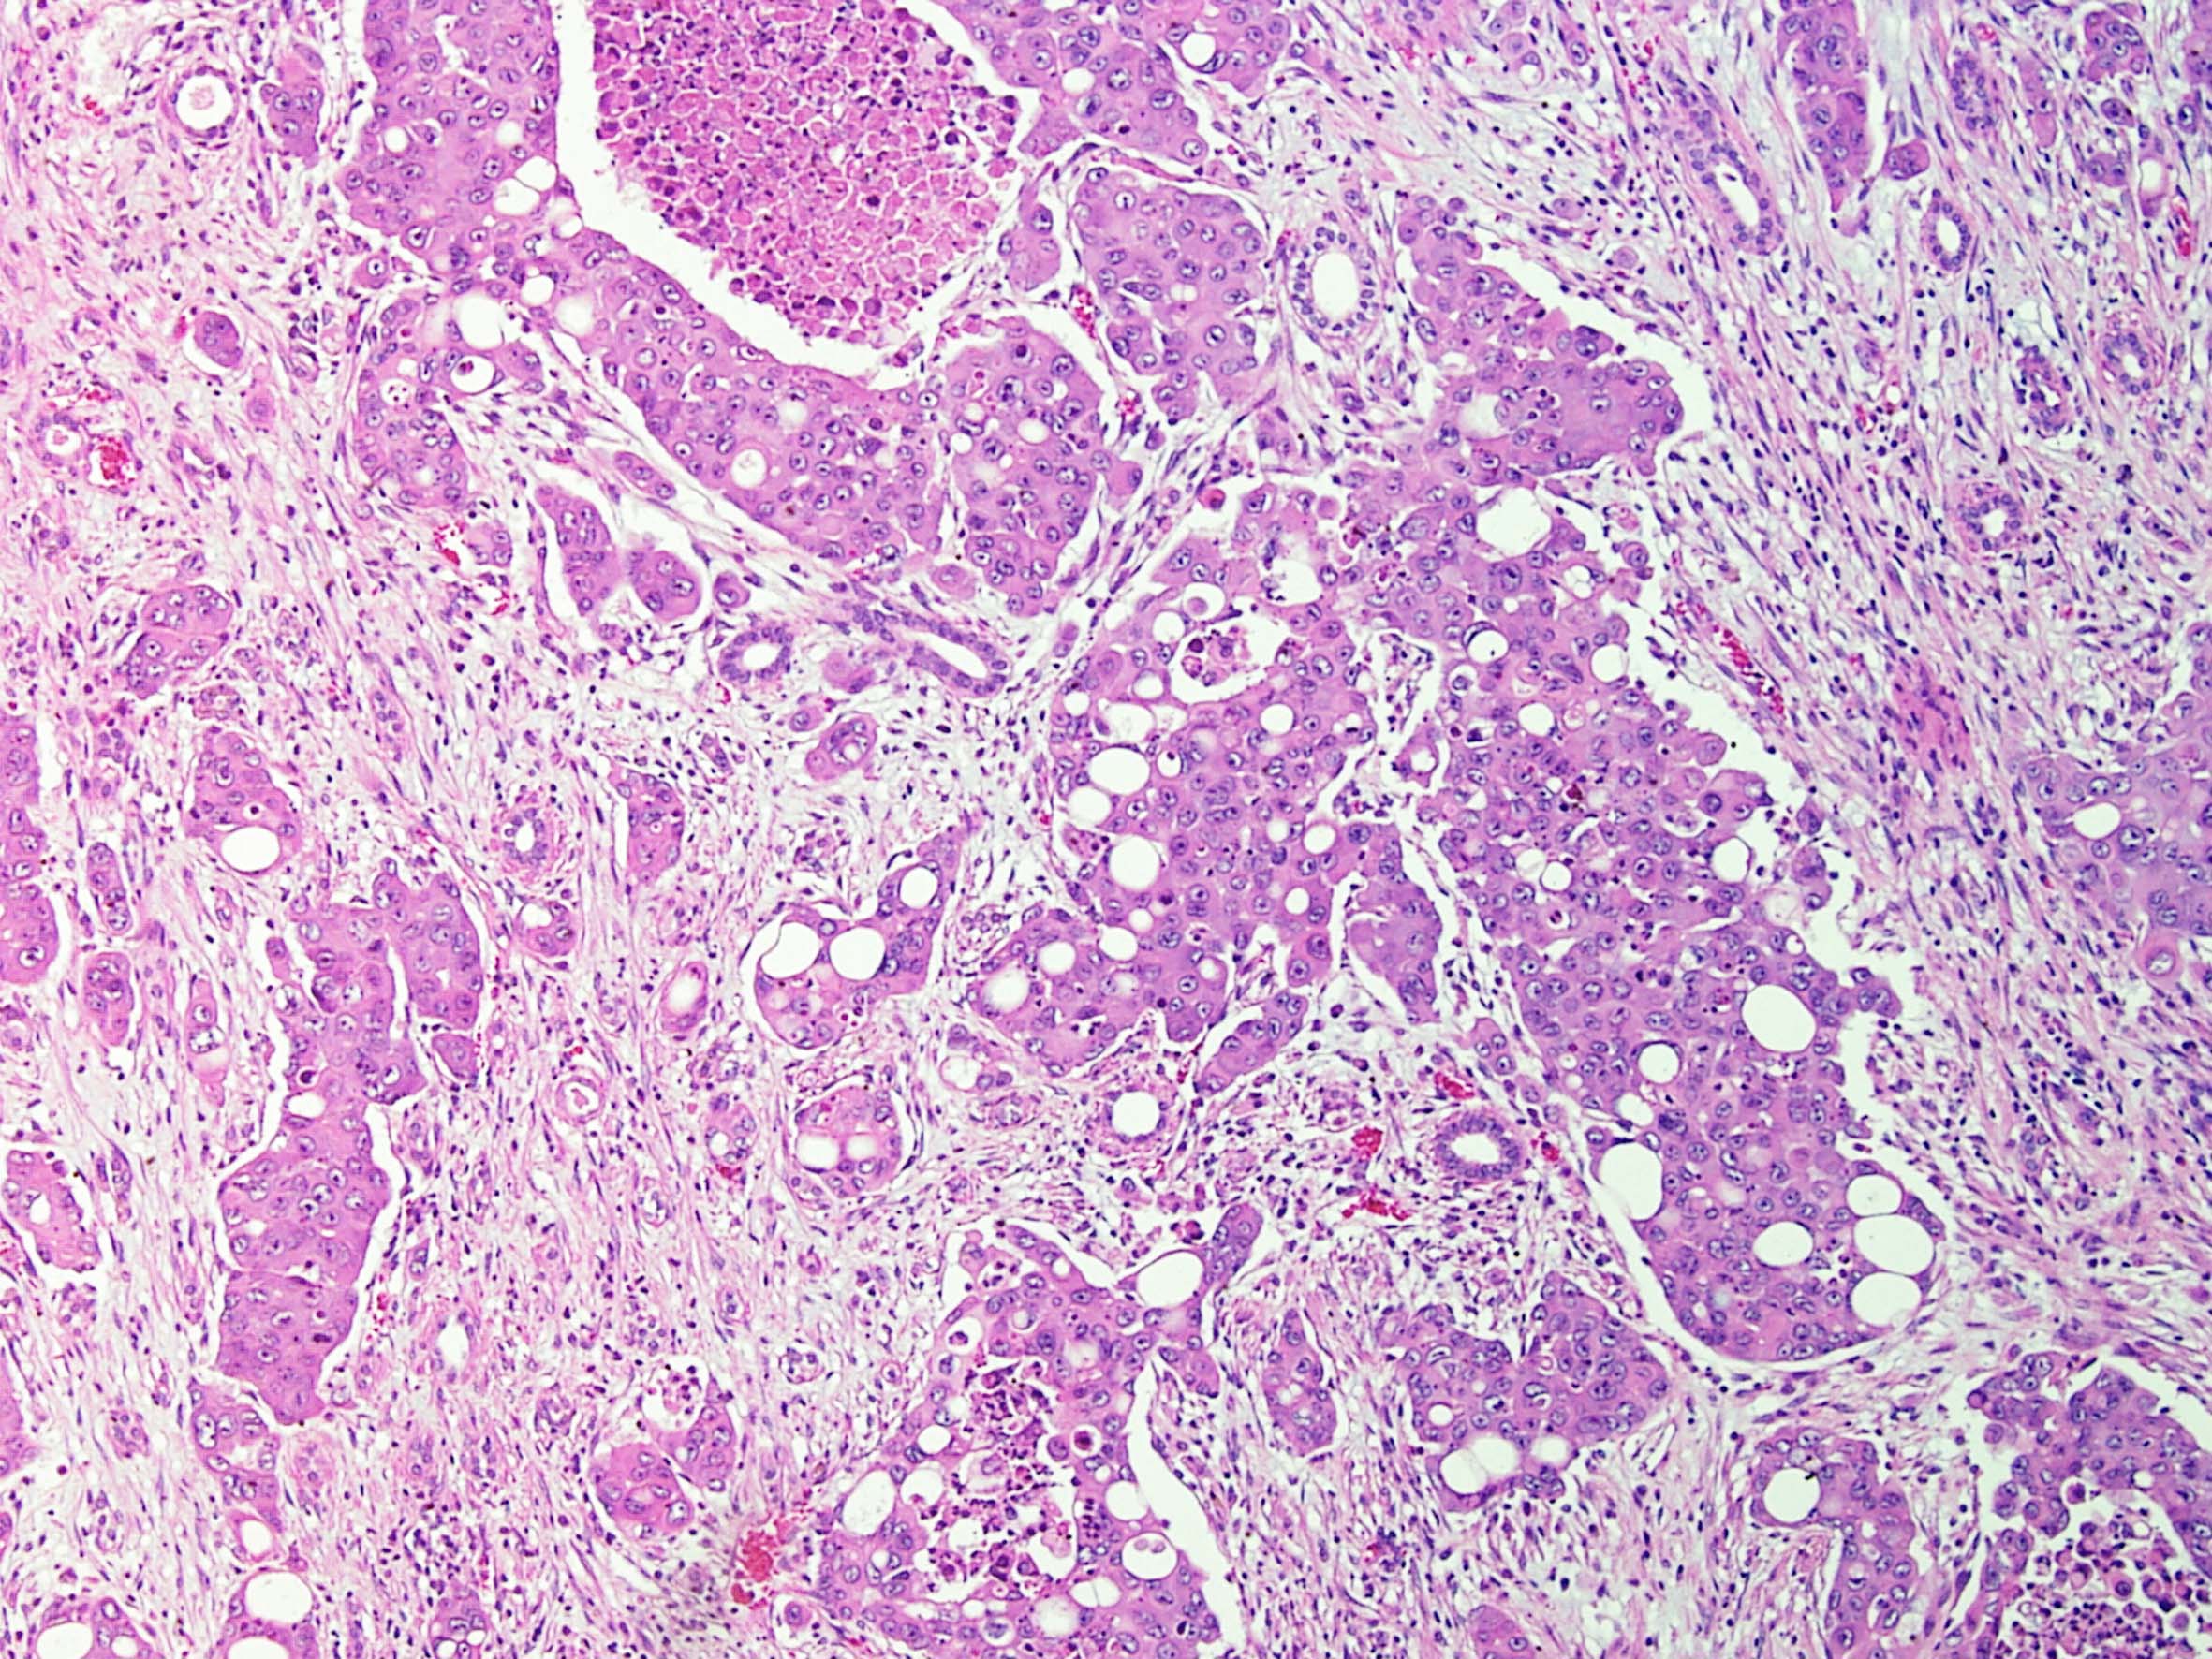

Consensus grade: Renal Medullary carcinoma

Renal medullary carcinoma